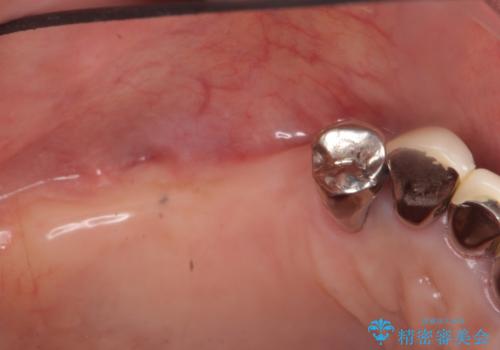

- 歯周病で失った奥歯や、グラグラしている歯の治療を希望され来院されました。

残すことのできない歯を抜去したのち、骨を造成し安定した環境下で長期的な予後を期待できるインプラント治療を計画します。